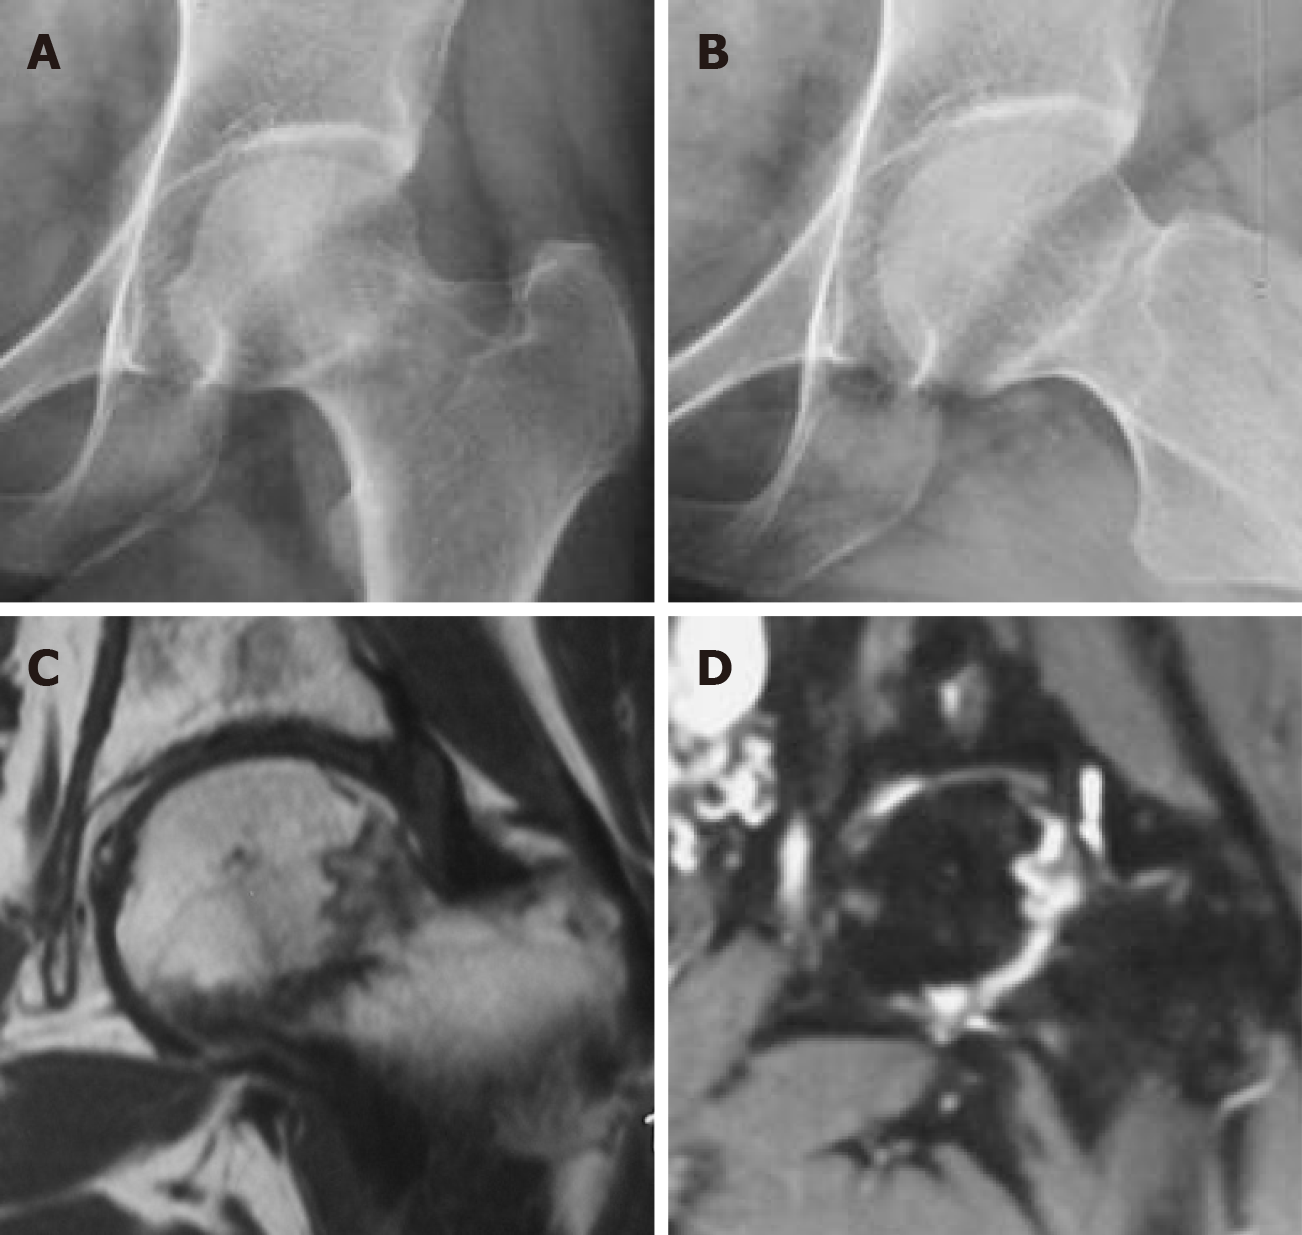

Figure 1

Figure 1 A 38-year-old woman presented at the hospital with left hip pain lasting for 3 months. She had a history of treatment with glucocorticoids for systemic lupus erythematosus. Based on the initial X-ray and magnetic resonance imaging, she was diagnosed with steroid-induced osteonecrosis of the femoral head. Conservative hip-preserving treatment was administered. A and B: X-Ray: The density within the left femoral head is uneven, with a clearly visible sclerotic zone. The joint alignment remains normal, and there are no significant changes in the joint space; C and D: Magnetic resonance imaging: No obvious collapse of the femoral head is observed. The left femoral head exhibits patchy and linear signal abnormalities, with low signal intensity on T1W1 and slightly high and low signal intensity on T2W2.